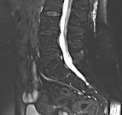

MRT – auch Kernspintomografie, oder Magnetresonanztomografie genannt – ist eine diagnostische Technik zur Darstellung der inneren Organe des menschlichen Körpers. Hier haben wir ein paar Bilder, um zu zeigen wie solche Aufnahmen mit dieser Technik aussehen.

Die Bilder sind nicht für diagnostische Zwecke geeignet!